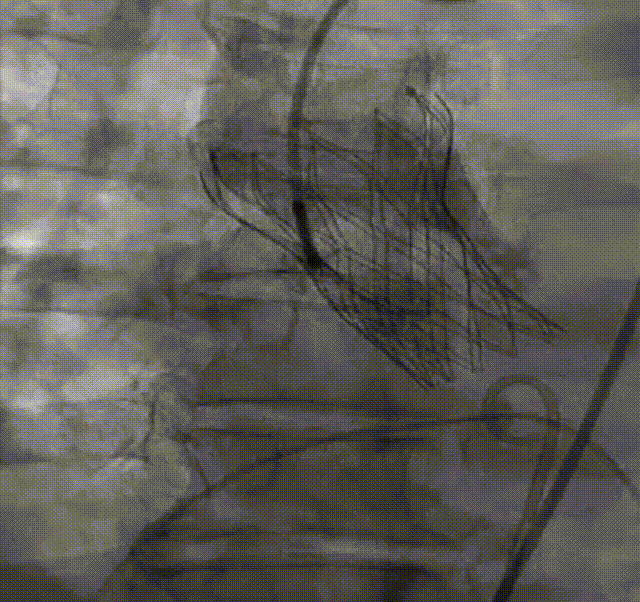

术后即刻造影

该临床试验结果已初步展示出该系统的稳定性和优异性能。5例病例涵盖了常见的各种解剖类型,包含2例Type 1型二叶瓣,1例Type 0型二叶瓣,2例不同钙化程度的三叶瓣,钙化积分最低的仅92,最高的HU850积分达到了1560,涵盖了不同手术难度和解剖类型的病变。这些持续的临床结果为未来机器人辅助TAVR手术的可行性和安全性提供了坚实的证据。